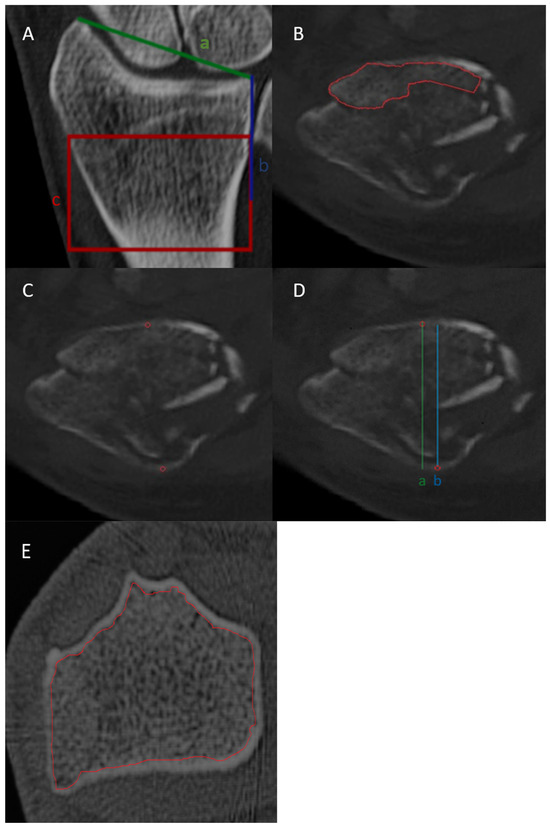

2.3. Image Interpretation

2.4. BMD Assessment